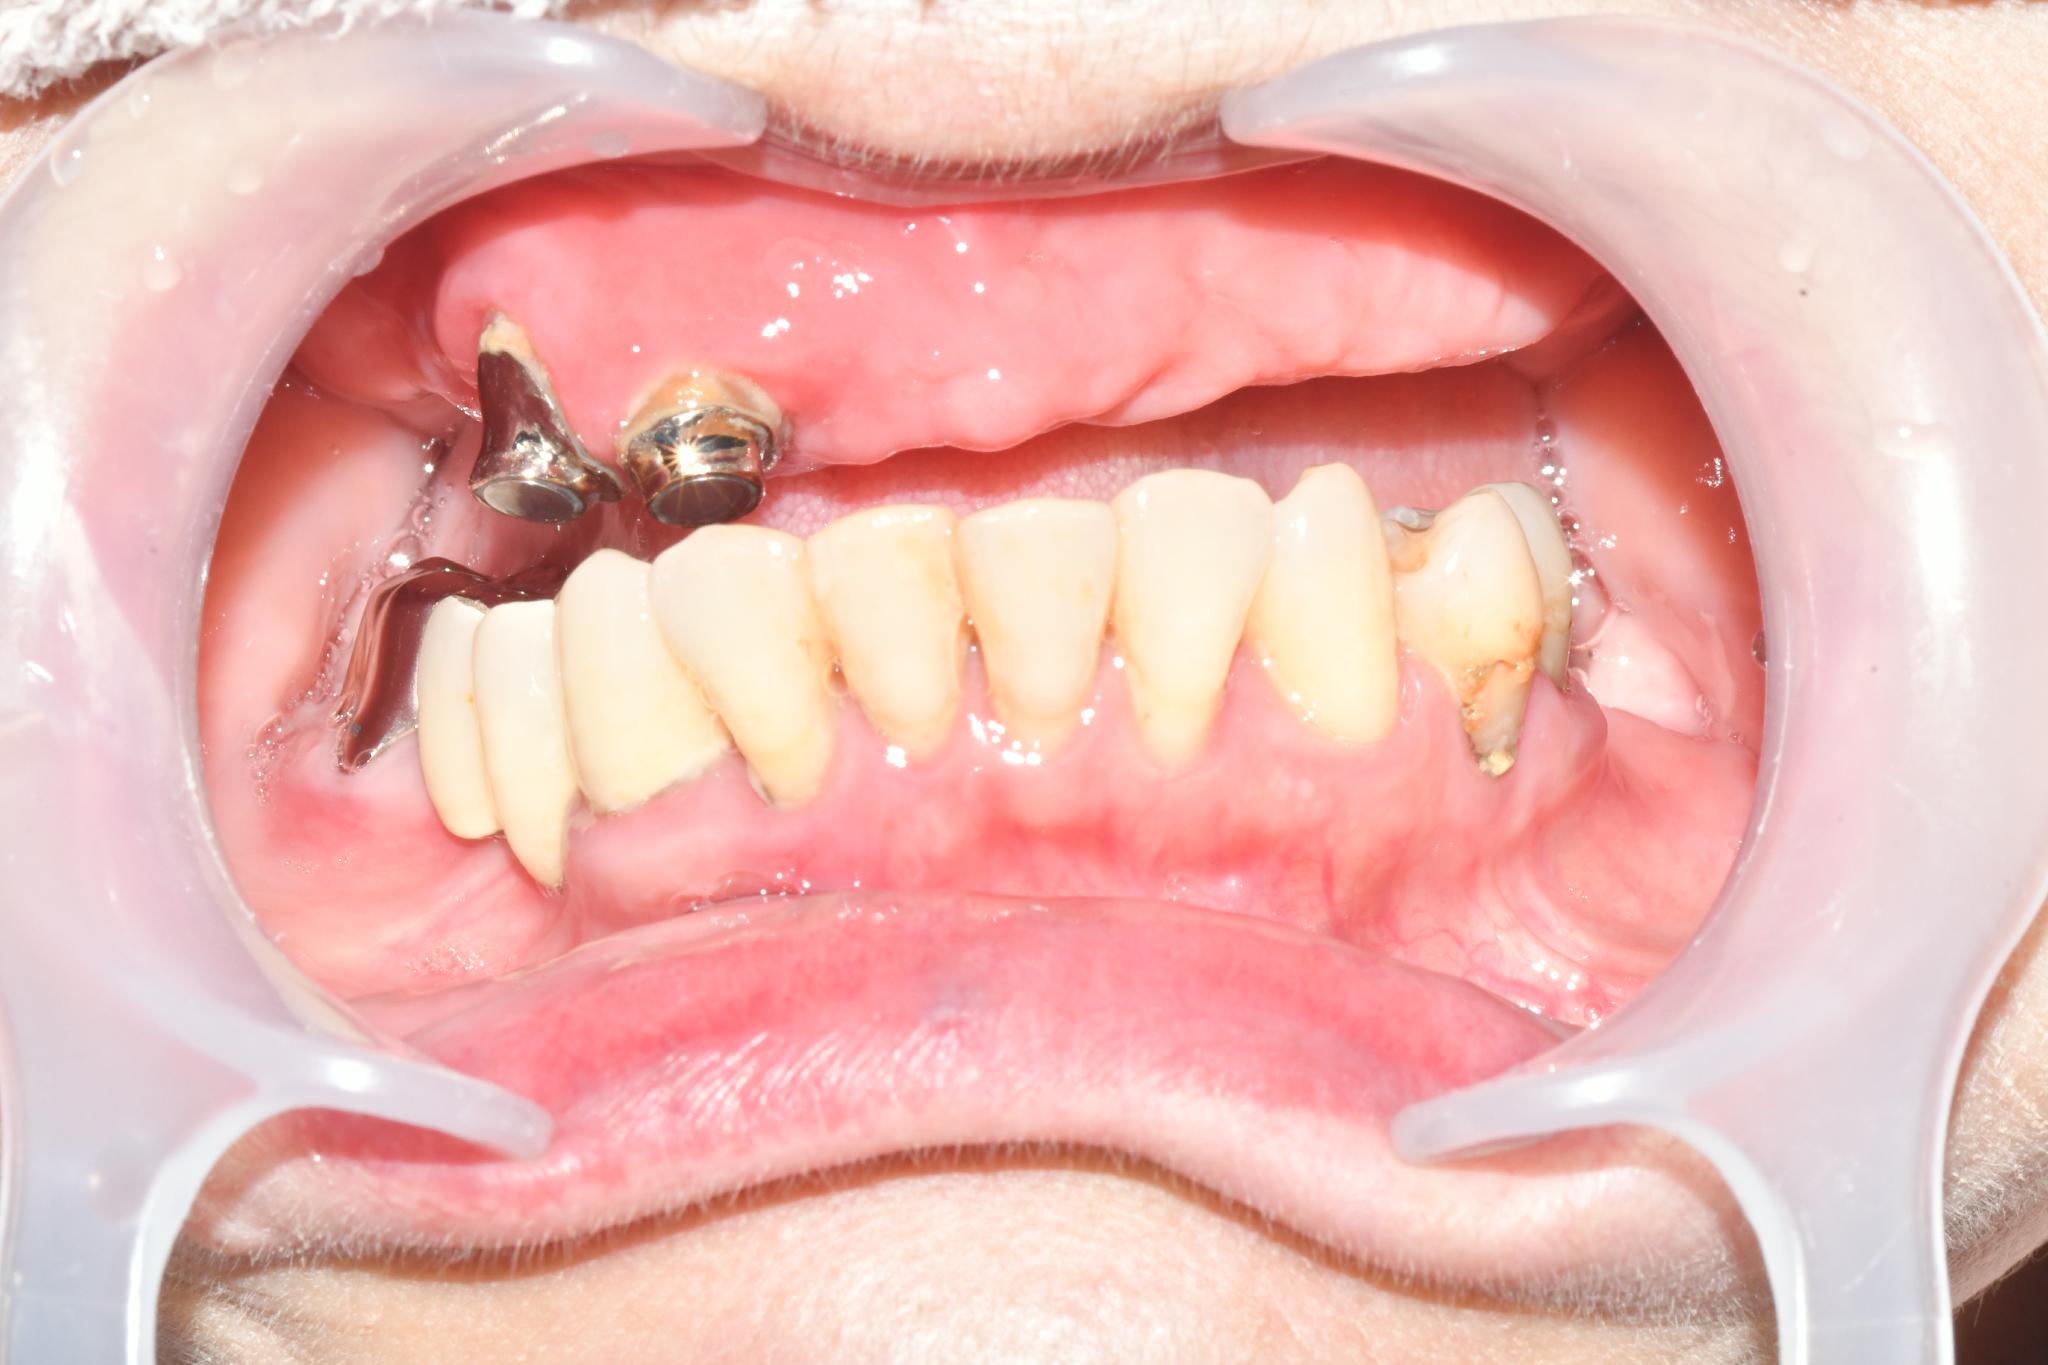

術前

内容 :上下顎オールオン4ザイゴマ2

費用 :5,899,850円

※モニター価格

期間 :半年

リスク:出血・腫れ・痺れ・痛み

磁石固定式の義歯を使用していましたが、頻繁に外れる上に痛みも伴い、機能的に限界を感じていました。特に、仕事柄「味見」をする必要があるのですが、義歯では満足に味を確かめることができず、支障が出ていました。食事の際も、食べ物が当たる度に歯茎に痛みもあり、日常生活においても深刻な悩みを抱えていました。

他院への相談もしましたが、将来的な維持管理や機能回復の確実性を考慮した結果、こちらでの治療を選びました。取り外し不要の固定式の歯になるオールオン4ザイゴマこそが、仕事と私生活の両立させるための唯一の手段だと確信し、手術を決意しました。

少し恐怖心はありましたが、スタッフの方の親切な対応のおかげでリラックスして臨むことができました。

手術当日に固定式の歯が入ったことに安堵しています。これから新しい歯に慣れていき、本来の咀嚼機能や、仕事で不可欠な「味覚を伴う味見」ができるようになることを期待しています。